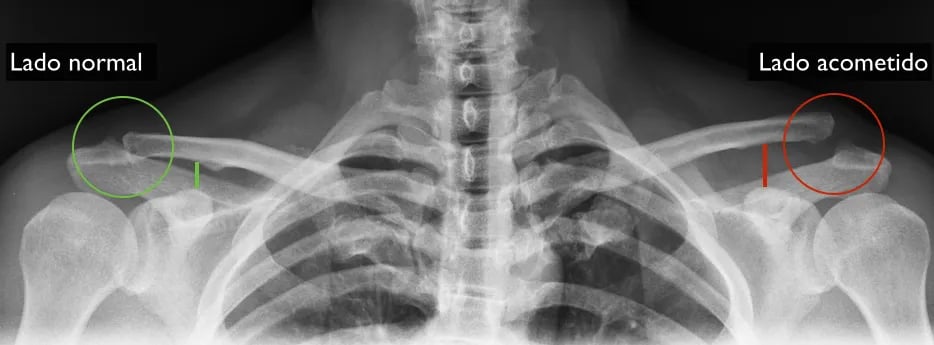

Luxação acromioclavicular é a perda de congruência entre a clavícula e o acrômio. Essa articulação é estabilizada por um ligamentos entre a clavícula e o acrômio e ligamentos entre o coracoide e a clavícula, que podem ser rompidos em traumas, em especial quedas sobre o ombro, causando a luxação acromioclavicular (LAC).